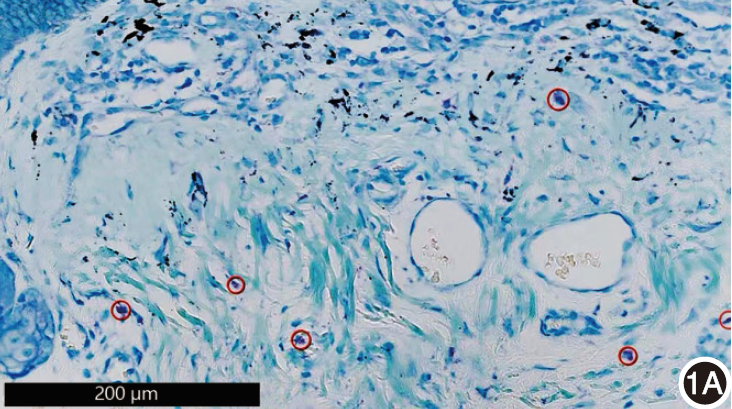

国内少见的双间新柱顶孢致皮肤感染4例

李美荣 唐旭华 吴榕 刘文韬 冯佩英

摘要 ( 197) PDF (19492 KB) ( 4)

DOI: 10.35541/cjd.20230579